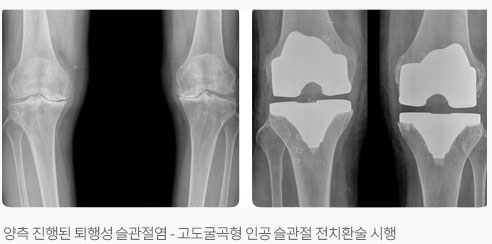

인공 슬관절 치환술이란?

인공 고관절 전치환술이 발달하고 결과가 좋아지면서 자연히 관절 마모가 심한 슬관절에도 인공 관절 치환술이 시행되어져 현재 많은 성공적인 디자인으로 좋은 결과를 보이고 있습니다.

인공 슬관절 전치환술은 슬관절 통증이 일상 생활을 할 수 없을 정도로 심하거나 통증 때문에 보조 기구를 사용해야 걸을 수 있는 사람, 슬관절 통증이 휴식과 상관없이 종일 지속되는 사람, 휴식을 취하거나 약을 복용해도 만성적인 염증이나 부종이 거의 감소되지 않는 사람, 무릎이 안쪽 또는 바깥쪽으로 구부러져 변형이 심한 사람, 무릎이 뻣뻣하고 무릎을 구부리거나 완전히 펴기 힘든 사람에게서 초기에는 통증 감소에 효과가 있던 비스테로이드성 약물(이부프로펜, 아스피린 등)이 이제는 더 이상 효과가 없는 사람, 진통제를 먹으면 위장장애가 너무 심하고 합병증으로 생활하기 힘든 사람들에게서 물리치료와 같은 다른 치료 요법이 효과가 없을 때 수술을 시행합니다. 인공 슬관절 치환술을 받은 환자들의 90%이상이 먼저 현저한 통증 감소와 변형의 교정 그리고 힘들었던 일상생활이 보다 편안하고 자유로와짐을 느낍니다. 산책, 수영, 골프, 운전, 가벼운 등산, 가벼운 자전거 타기 등의 활동을 거의 통증 없이 수행할 수 있습니다. 인공 관절의 특징으로 환자는 수술 상처 부위의 피부 감각이 다소 무뎌졌음을 느낄 수 있습니다. 또한 과도하게 관절을 구부릴 때에 약간 뻣뻣한 감을 느낄 수도 있고, 무릎을 완전히 꿇는 것은 불편하지만 점차 가능해집니다. 때때로 무릎을 구부리거나 펼 때 금속과 플라스틱이 부딪히는 소리가 날 수도 있으나 시간이 지날수록 감소되며, 수술 전에 겪었던 통증이나 기능 장애에 비하면 조그마한 문제에 지나지 않습니다. 수술 후 규칙적으로 가벼운 운동 프로그램에 반드시 참가하여, 근력을 강화시키고 인공 관절이 신체에 잘 적응되도록하고 낙상과 상해 방지를 위해 각별히 조심해야 합니다. 치아 검진을 받을 때 반드시 인공 관절 수술한 것을 말해주어야 사전에 항생제를 복용하여 예상되는 감염을 막을 수 있습니다. 정기적으로 병원을 방문하여 정형 외과 의사의 검진을 받아야 합니다. 대개 60세 이상의 나이에 X-선상에서 연골이 완전히 닳아 없어져 뼈와 뼈끼리 부딪히는 상태에서는 거의 통증이 약으로는 조절이 안되며 걸을 때 심하게 아프다고 호소합니다. 이런 경우에 인공 슬관절 치환술을 시행하여 휜다리를 바로 잡아주고 마모된 연골을 인공 대치물로 바꾸어 주면 통증이 사라지고 정상적인 보행을 가능하게 하여 줍니다. 무릎 인공 관절의 수명은 과거에는 5~10년 정도 후에 반드시 재수술을 해야 한다고 했으나, 현재는 그보다 더 오랜기간까지도 사용이 가능한 것으로 알려져 있으며, 인공 관절의 수명 때문에 수술을 꺼릴 필요는 없다고 봅니다. 수술 후 다음날(한쪽 다리만 수술했을 경우) 무릎을 굽혔다 폈다 할 수 있도록 만들어진 기계를 통해 환자 스스로 움직이는 연습을 시작할 수 있습니다. 양쪽 다리를 모두 수술한 경우에는 수술 후 이틀째부터 시작합니다. 걷는 연습은 한쪽다리의 경우 2~3일째부터, 양쪽 다리는 5~7일째부터 연습을 시작합니다. 퇴원은 한쪽다리의 경우는 수술 후 2주, 양쪽 다리의 경우는 3~4주경 입니다. 퇴원 시에는 목발이 없이도 정상인과 비슷한 보행을 할 수 있게 됩니다. 수술 후 3개월까지는 병원에서 준 약을 복용해야합니다. 퇴원 후 대게 1~2개월까지는 붓고 열감이 있으므로, 붓기를 가라앉히기 위한 얼음 찜질을 하고, 물리치료도 좋지만 순환을 위해 자주 목욕탕에 가는 것이 좋습니다. 목욕 후에는 역시 얼음 찜질을 해야 합니다. 붓기가 가라앉고 열감이 없으면 온찜질을 하고, 술은 3개월까지 삼가하고 미끄러지거나 넘어지지 않도록 주의 해야합니다.